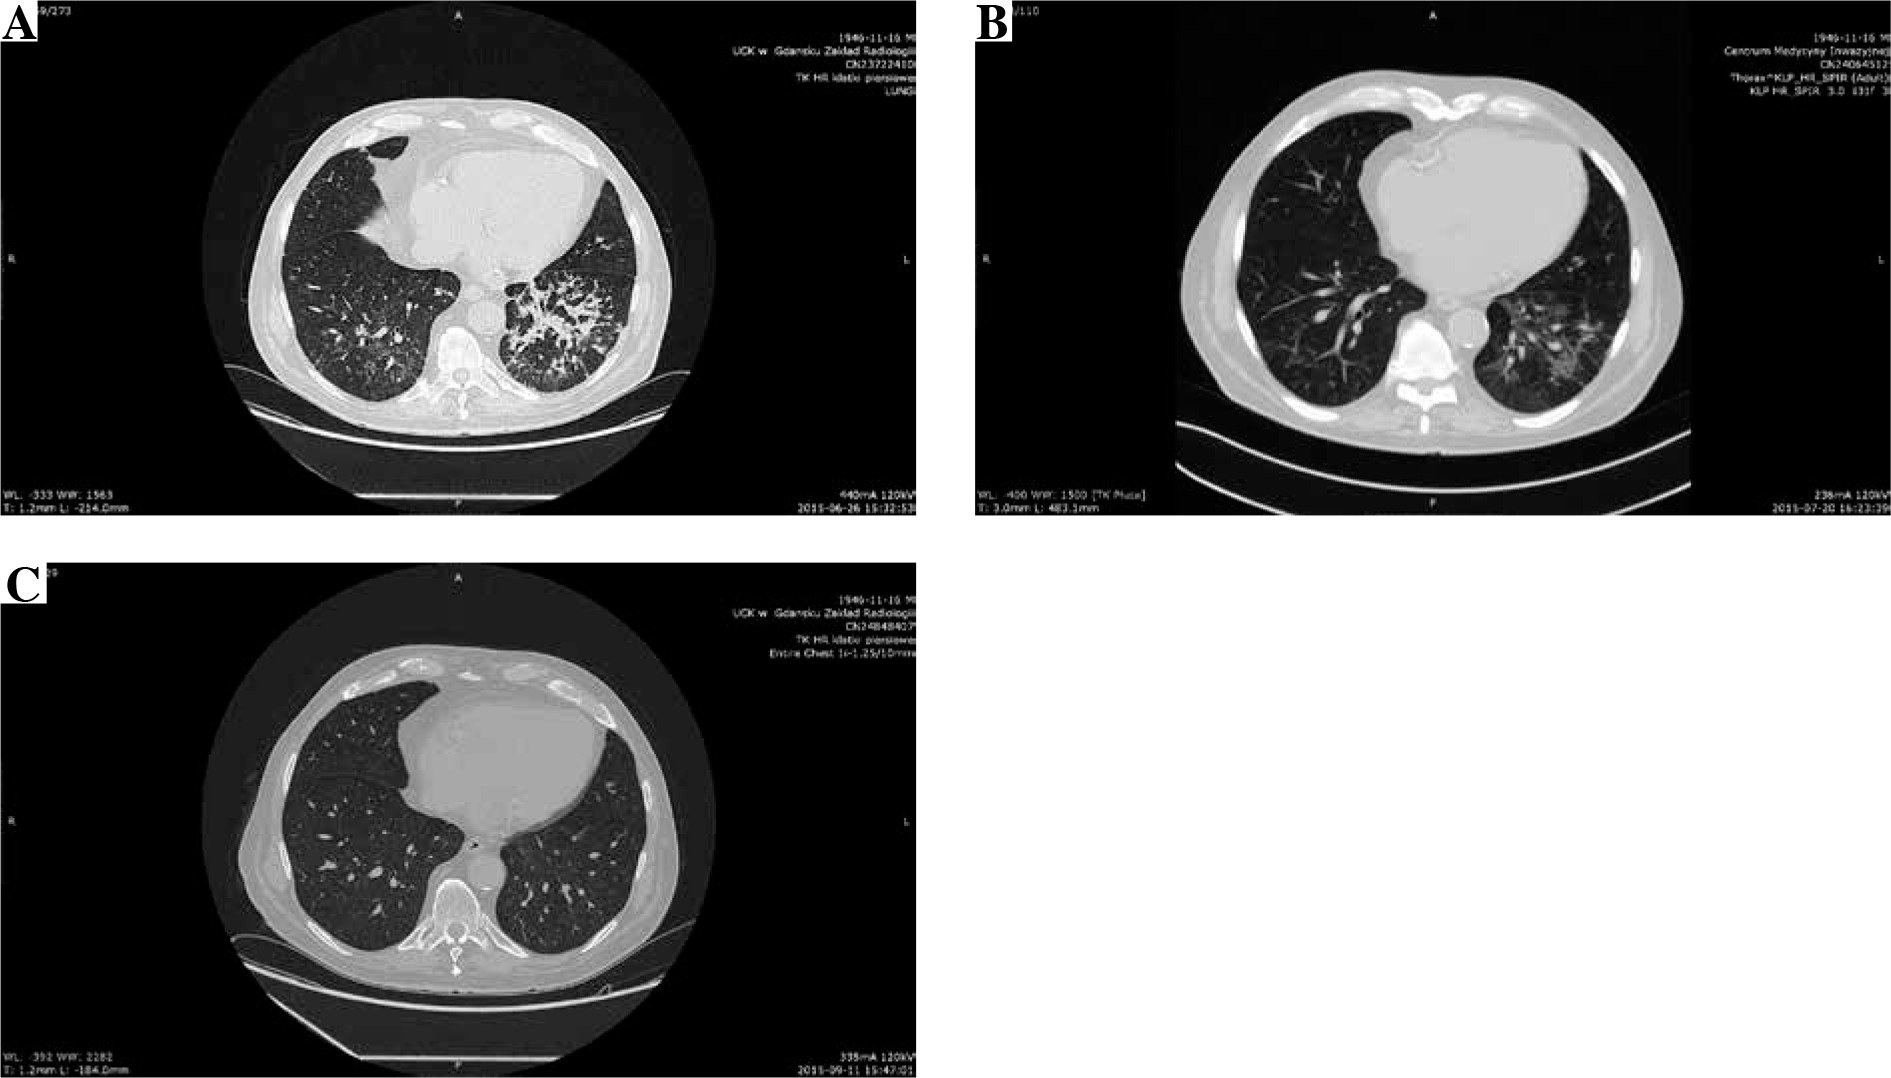

He initially received amoxicillin/clavulanic acid. Bacterial cultures of blood and urine were negative. The symptoms improved, and fever resolved, with a decrease in both WBC and CRP levels over the next few days with empiric antibiotic treatment. There was clinical improvement, but without a radiological resolution. An HRCT scan (Fig. 1A) revealed a disseminated nodular pattern in both lungs, accompanied by peribronchial consolidations and lung parenchyma retraction dominating in the lower lobes. No pleural effusion was seen. Bronchoscopy was unremarkable. A transbronchial biopsy revealed mild nonspecific inflammation with areas of fibrosis in the bronchial walls. Bronchoalveolar lavage was sent for cell count, bacterial and viral culture, and fungal and acid-fast bacillus analysis. Both sputum and bronchoalveolar lavage cultures were positive for Achromobacter denitrificans. After a complete diagnostic workup including repeated bacterial and mycobacterial cultures, QuantiFERON1-TB Gold test, blood CMV-PCR, blood Aspergillus galactomannan and Candida mannan, immunofluorescent staining of bronchoalveolar fluid for Pneumocystis jiroveci, other pulmonary opportunistic infections were ruled out, and a diagnosis of A. denitrificans pneumonia and EVR pulmonary toxicity was made. A 17-day course of piperacillin/tazobactam chosen according to the susceptibility profile (Table 2), and a reduction of the EVR dose to the target trough levels of 2.8-3.2 ng/ml resulted only in partial resolution of radiological abnormalities confirmed by HRCT (Fig. 1B). After three weeks of antibiotic treatment EVR was withheld. EVR discontinuation with no additional antibiotic treatment resulted in complete recovery and a complete resolution of pulmonary infiltrates in an HRCT performed at a further 10-week follow-up (Fig. 1C). The immunosuppressive regimen on discharge was restricted to cyclosporine and glucocorticosteroids.

Fig. 1

A) Initial computed tomography (CT) of the lungs shows poorly defined bilateral patchy consolidations without pleural effusion, B) chest CT after 3-week antibiotic treatment and everolimus (EVR) dose reduction shows only partial resolution of bilateral patchy consolidations, C) CT performed 10 weeks after EVR discontinuation shows complete resolution of symptoms